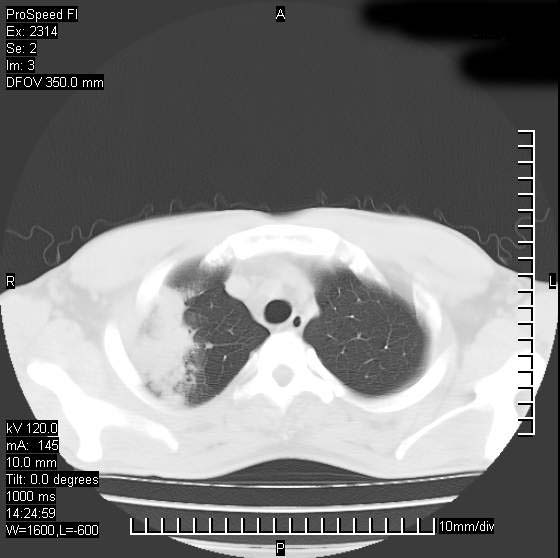

男性,再生障碍性贫血,入院前发热10天,最高40c,右侧胸痛,外院ct示右上,中肺边缘模糊的球性影(就是我现在图中标示的范围),考虑炎症,在我院使用头孢呋辛,洛美沙星10天,高烧消退,自感下午稍有发热,但今天ct示右上,中肺病灶明显扩大,还是考虑炎症,看其中的球型影是否霉菌感染??,是否能排除结核?

右肺中叶外侧段病变,上缘界限不清,下缘锐利,以段性发病为主,内见巨大空洞及空洞内容物,结合病史首先考虑:化脓性肺炎。不除外霉菌感染!

片状高密度影内见空洞影,内可见球形软组织密度影,并有新月征,考虑霉菌感染.